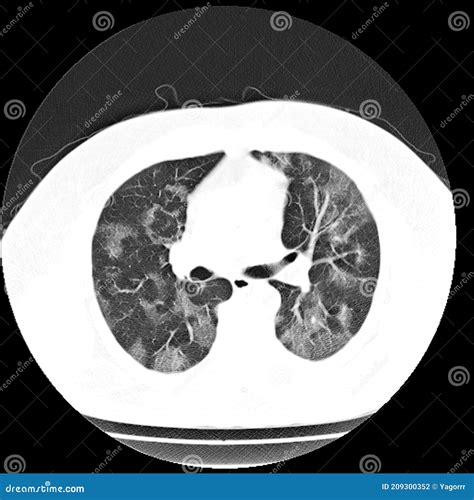

Once the scan is completed, a radiologist will interpret the images and generate a report. When viewing a Pneumonia CT Scan, medical professionals look for specific patterns of lung involvement. These patterns often indicate the type of pneumonia or the severity of the inflammatory response.

Common findings often described in reports include:

• Consolidation: This refers to the filling of air spaces (alveoli) with fluid, pus, or other material, appearing as dense, white areas on the scan.

• Ground-Glass Opacity (GGO): A hazy appearance in the lungs, indicating partial filling of air spaces or thickening of the lung interstitium. This is often seen in viral pneumonias.

• Bronchograms: The appearance of air-filled bronchi surrounded by consolidated lung tissue.

• Pleural Effusion: The buildup of fluid in the space between the lung and the chest wall.

• Nodules or Cavitation: These findings may prompt further investigation to rule out other infections or malignancy.

It is important to remember that these findings must always be correlated with the patient's symptoms, laboratory results, and clinical history. A report with "positive findings" does not always imply a worst-case scenario, as many patterns are typical of common bacterial or viral infections.